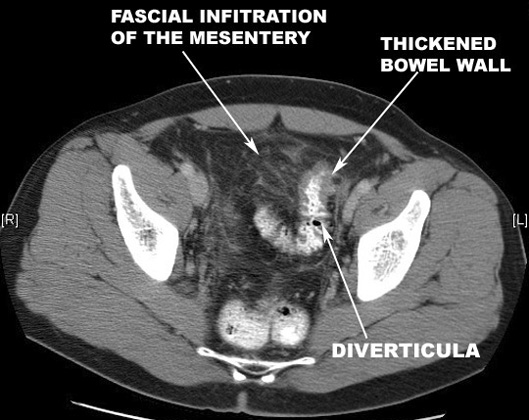

Acute Diverticulitis: A section of colon reveals acute inflammation (hyperemia, swelling) of the serosa and pericolic fat. |